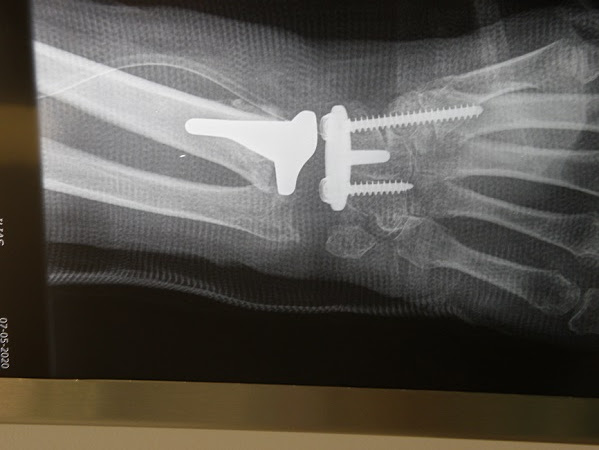

« Η μέθοδος πράγματι αποτρέπει τις αναπηρίες των καρπών μετά από σοβαρούς τραυματισμούς και δίνει εκ νέου κίνηση των δακτύλων και χρήση του καρπού » αναφέρει ο διαπρεπής Χειρουργός Ορθοπεδικός- Μικροχειρουργός Χεριού , Δρ. Ιωάννης Α. Ιγνατιάδης, Διευθυντής Κλινικής Μικροχειρουργικής Άκρων στο Ιατρικό Ψυχικού, που μαζί με την ομάδα του εφαρμόζει τη μέθοδο «πρόθεσης ελεύθερης κίνησης» (freedom), αφού ήταν αυτός που πραγματοποίησε την πρώτη επέμβαση στην Ελλάδα.

Οι επεμβάσεις αυτές (μόνιμη αρθροδεσία με πλακόβιδο και εγγύς καρπεκτομή ) παρουσίαζαν όμως σοβαρά λειτουργικά προβλήματα στις κινήσεις του χεριού.

Σύμφωνα με τον κ Ιγνατιάδη « η αρθροπλαστική καρπού παρουσιάζει το σοβαρό πλεονέκτημα απέναντι στην αρθροδεσία ότι διατηρείται η κίνηση του καρπού, ενώ στην αρθροδεσία ναι μεν εξαλείφετε ο πόνος και διατηρείτο η ισχύς, πλην όμως καταργούνταν εντελώς η έκταση-κάμψη του καρπού, στη δε εγγύς καρπεκτομή είχαμε μεν κίνηση αλλά υπήρχε σχετική αστάθεια και έλλειψη ισχύος».

Η ομάδα του κ Ιγνατιάδη εφαρμόζει το μοντέλο «ΕΛΕΥΘΕΡΗΣ ΚΙΝΗΣΗΣ» ή “FREEDOM” το οποίο επιτρέπει κίνηση προς όλες τις κατευθύνσεις. Όχι μόνο έκταση-κάμψη, επιτρέπει και ανύψωση βάρους 8-10 κιλών μετά το πρώτο χρόνο από την εφαρμογή του.

Στο 90% των περιπτώσεων δεν χρειάζεται ιδιαίτερη παραγγελία για το υλικό(custom made), δεδομένου του ότι στο σετ υπάρχουν όλα τα μεγέθη και το υλικό είναι σχεδόν έτοιμο(modular). Σε νέα άτομα η ενσφήνωση γίνεται χωρίς ειδικό τσιμέντο, ενώ σε μεγάλες ηλικίες χρησιμοποιείται κατά την τοποθέτηση ιατρικό τσιμέντο(δίκην πορσελάνης).